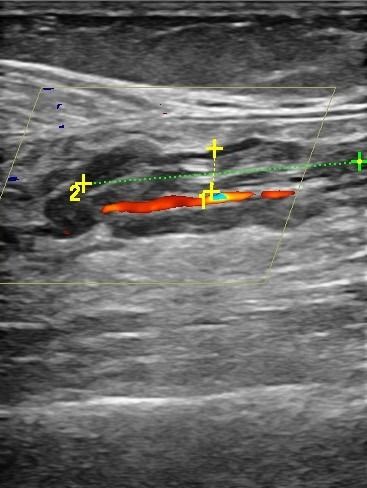

Με το Triplex Αρτηριών Κάτω Άκρων μπορούμε να αξιολογήσουμε αν υπάρχει παθολογία στις αρτηρίες. Συνήθεις παθολογίες στις αρτηρίες είναι τα ανευρύσματα και οι στενώσεις. Με το Triplex μπορούμε να υπολογίσουμε με ακρίβεια το βαθμό στένωσης στις αρτηρίες και να διαπιστώσουμε αν υπάρχει απόφραξη. Η δυνατότητα διάγνωσης παθολογιών στις αρτηρίες των κάτω άκρων με τη χρήση του Triplex είναι πολύ χρήσιμη για την αντιμετώπιση αγγειακών προβλημάτων, καθώς πρόκειται για παθήσεις που μπορούν να οδηγήσουν σε σοβαρές συνέπειες αν δεν ανιχνευθούν έγκαιρα.